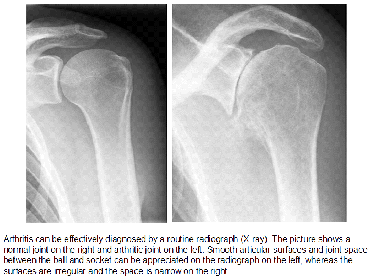

X-Rays

X-rays are imaging tests that create detailed pictures of dense structures, like bone. They can also help distinguish among various forms of arthritis.

X-rays of an arthritic shoulder will show a narrowing of the joint space, changes in the bone, and the formation of bone spurs (osteophytes).